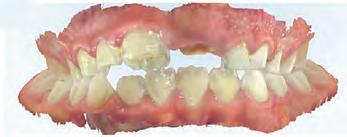

A 77-year-old Caucasian patient presented to the dental clinic after five years without dental care. The clinical findings showed significant bone loss, chronic periodontitis, and loss of some teeth that stabilized the occlusion. The patient reported cold sensitivity in tooth #46, especially when ingesting liquids.

Periapical X-ray confirmed the findings of the clinical examination and root caries was also detected in the distal root of tooth #46, which answered positively to the sensitivity test (Fig.1-2).

The treatment plan began with a focus on returning the patient to adequate periodontal health. In a subsequent session, with improved condition of the periodontium, the restoration of tooth #46 was performed. Under block anesthesia of right inferior alveolar nerve and rubber dam isolation, the amalgam restoration was completely removed and access to the caries cavity obtained (Fig. 3-5). Despite the proximity to the pulp tissue, no exposure occurred, and the class II cavity was fully restored with Biodentine™ (Fig. 6-8).